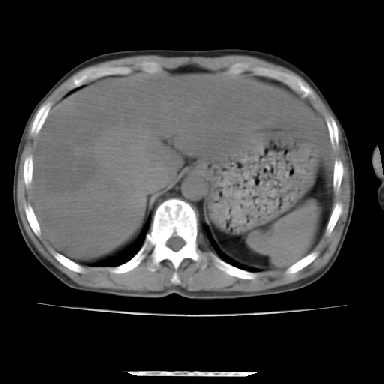

标题: CT7372:脂肪肝?外伤? [打印本页]

标题: CT7372:脂肪肝?外伤?

m 45 车祸,硬膜下血肿

窗宽太宽,调低点就好了,应该是不均质脂肪肝表现,请结合临床,单纯肝挫伤  其内无出血灶很少见,必要时做mri检查

窗宽太大,对比度太差了。局限性脂肪肝也有可能,但是亦不排除外伤性改变,增强扫描应该也还可以鉴别的。

肝内未见出血灶,但不能除外外伤性肝损伤,所示层面应考虑弥漫性脂肪肝.请结合临床必要时做mir检查

肋骨无骨折,腹腔未见游离液体,所以不均匀脂肪肝首先考虑,但如果病人情况允许还是做个增强检查放心

考虑不均匀性脂肪肝,肝包膜下光整,肋骨无异常,无腹水征,不支持肝挫伤。